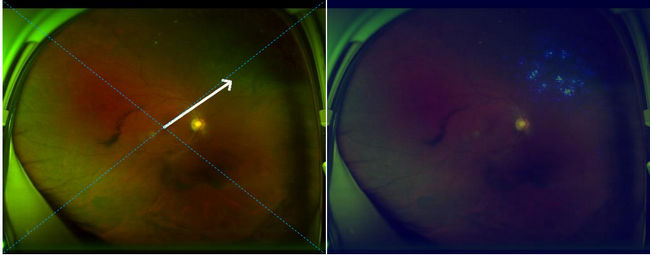

超廣域眼底彩照人工智能眼病篩查系統:圖中右側高亮區域為篩選出來的病變

左側圖片箭頭指處為視網膜脫離,右側圖片高亮區域熱圖提示視網膜脫離的精確位置

這款系統不僅能對眼底圖像進行解讀,同時可以自動標出病變部位,有助于醫生有針對性的解讀報告。同時如果視網膜脫離檢查結果呈陽性,系統會自動給予體位指導,以延緩視網膜脫離的進展,降低手術并發癥,改善患者的視力預后。